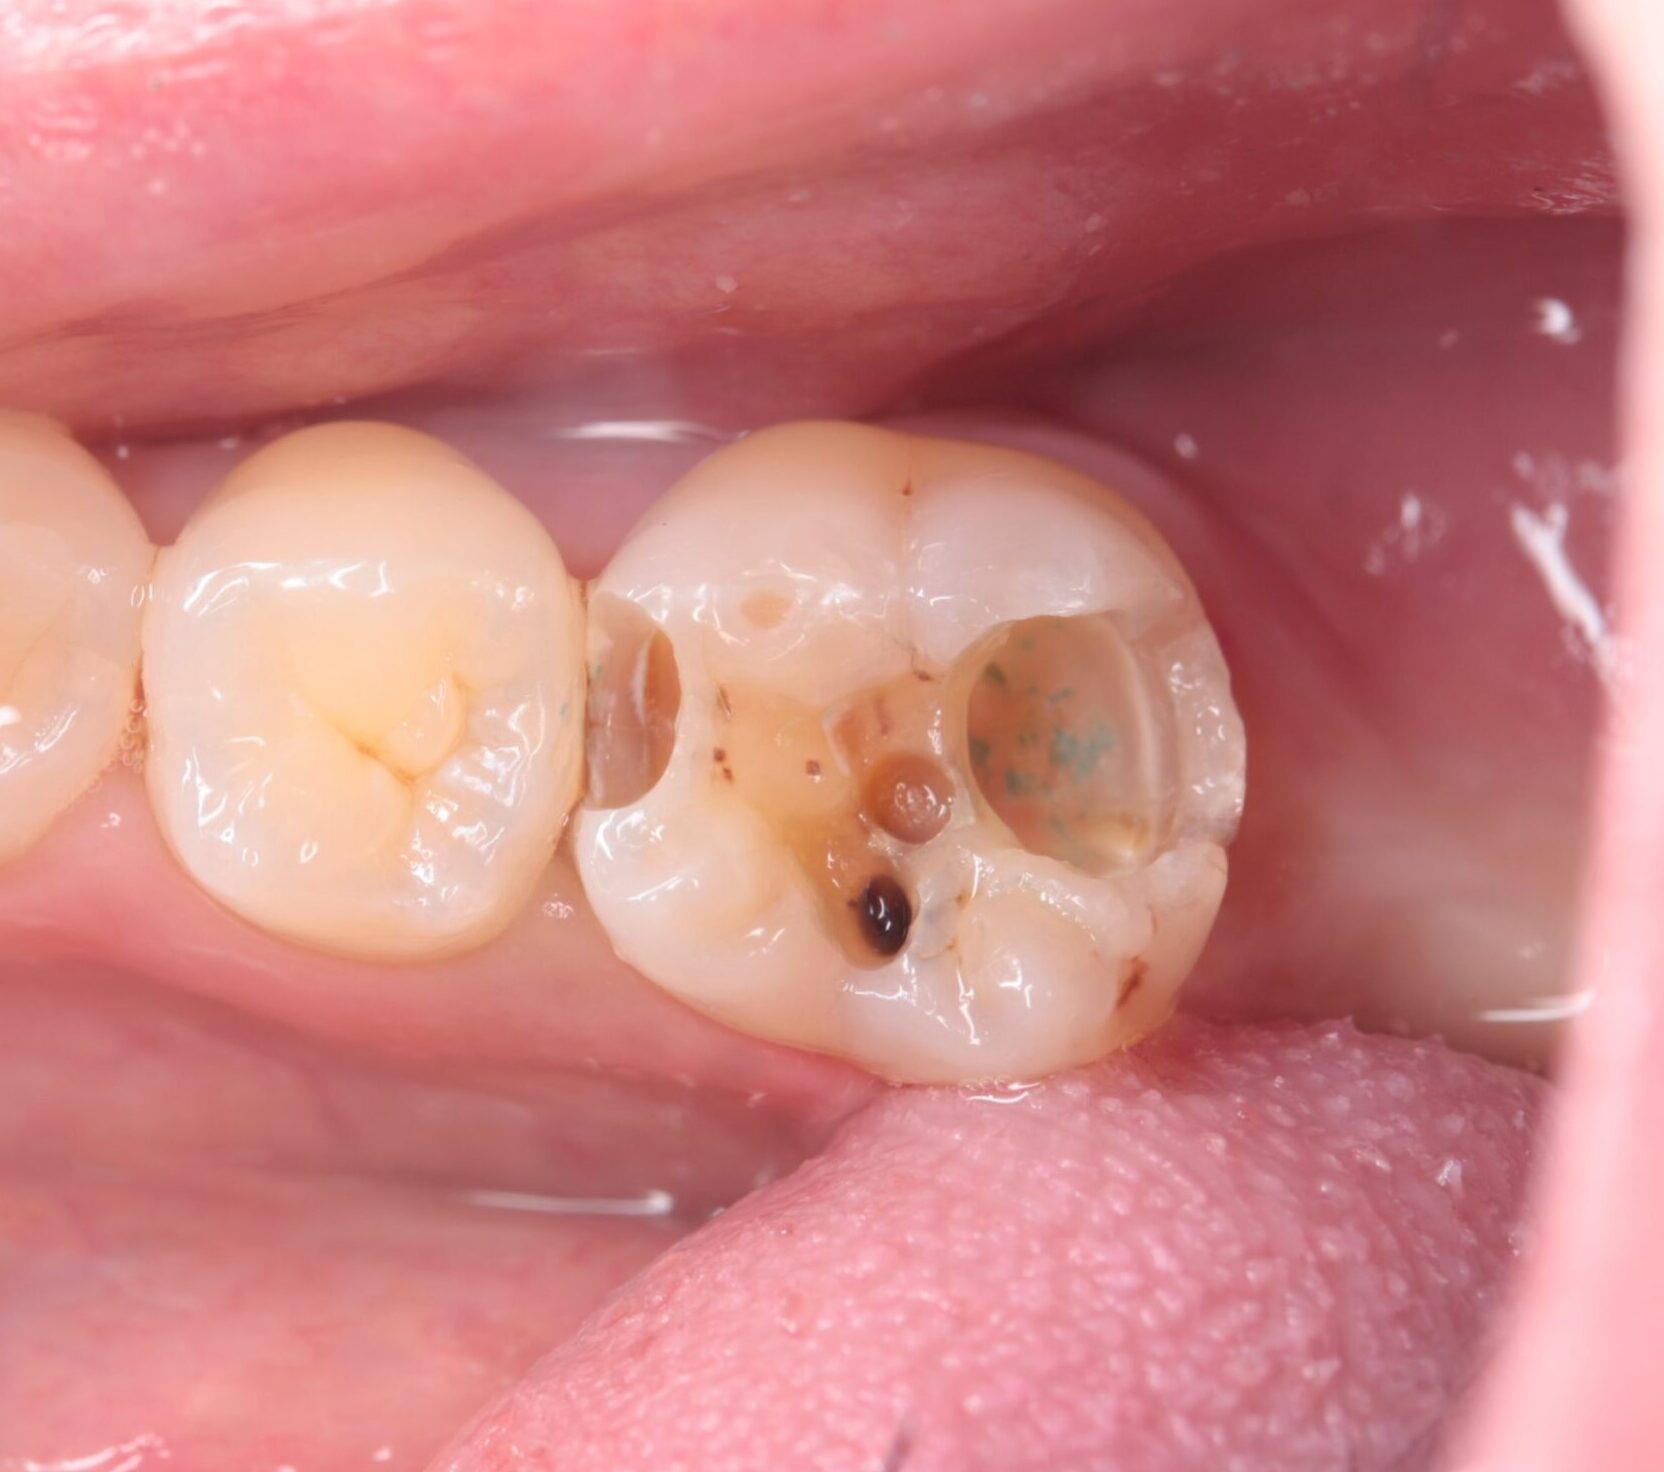

むし歯除去

むし歯が青く染まる液(う蝕検知液)を使用し、感染した歯質を確認しながら慎重に除去しました。

この時点では神経が完全に露出していたわけではありませんが、かなり近い位置までむし歯が進行していました。そのため、すぐに神経の治療へ進むのではなく、まずは仮の詰め物で1〜2週間ほど経過を確認しました。

しかし、その後強い痛みが出たため、神経を残すことは難しいと判断し、根管治療へ移行しました。 -